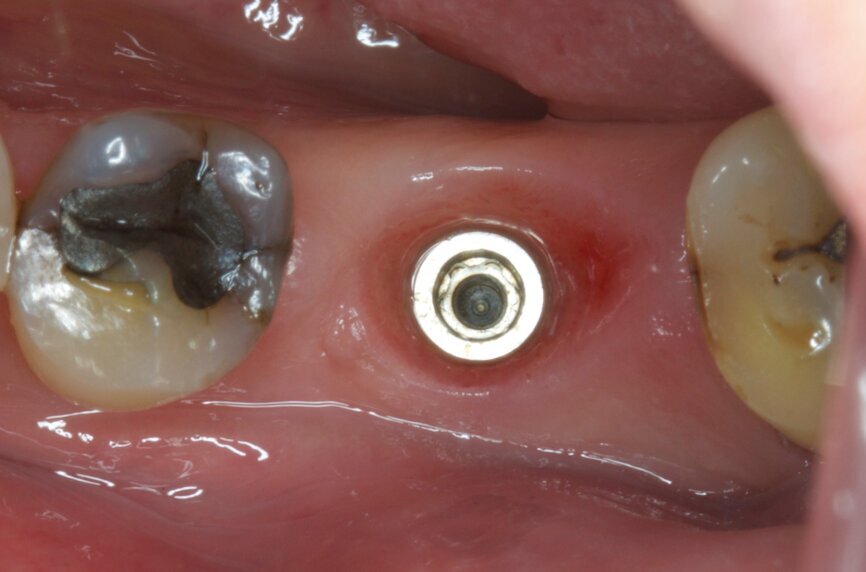

Fig. 16: Sutures to stabilise the biomaterials in place.

Fig. 21: Gingival healing ready for initiation of definitive crown.

It was possible to verify solid interradicular bone availability (Fig. 5), extending further the limits of the root apices and allowing for a centrally oriented osteotomy. The implant bed preparation started with the use of a needle drill at 800 rpm, followed by the ⌀ 2.2 mm and ⌀ 2.8 mm drills (Figs. 6–10). The implant was placed with the use of ratchet and torque control, reaching the desired final position at a 50 N cm torque value (Figs. 11–13). The socket was then augmented with bovine-derived bone substitute impregnated with advanced platelet-rich fibrin (A-PRF) and finalised with sutures to keep the A-PRF application immobile, and a 3 mm healing abutment was placed (Figs. 14–17).